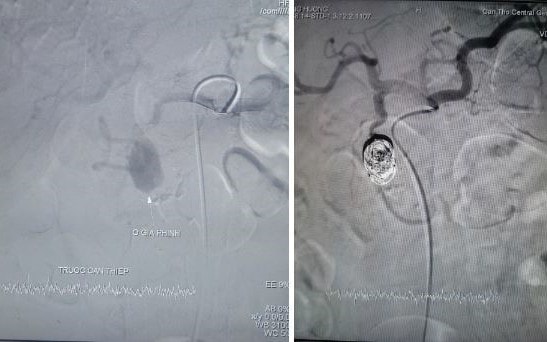

PLBĐ - Bệnh viện Đa khoa Trung ương (BVĐKTƯ) Cần Thơ vừa can thiệp thành công, cứu sống bệnh nhân xuất huyết tiêu hóa do vỡ ổ giả phình kích thước lớn từ nhánh động mạch vị tá tràng, bằng phương pháp can thiệp nội mạch.

PLBĐ - Ngày 18-10, thông tin từ Bệnh viện Đa khoa (BVĐK) Trung ương Cần Thơ cho biết nơi đây vừa can thiệp nội mạch thành công cho bệnh nhân xuất huyết tiêu hóa do vỡ ổ giả phình kích thước lớn từ nhánh động mạch hiếm gặp.